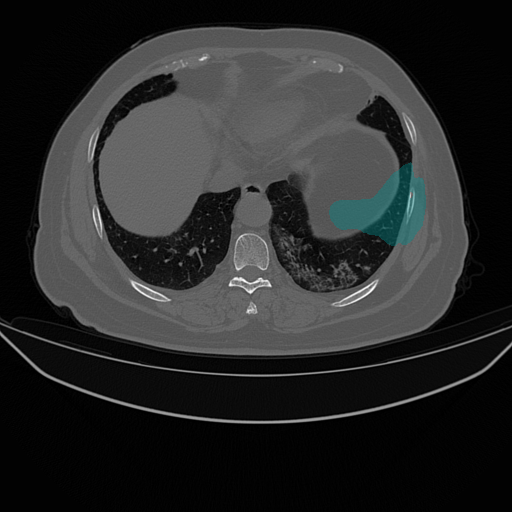

| Lung Segmentation (COV, 2019) Left lung (Cyan) Right lung (Yellow) | ![]() |

| (e) CT slice | (f) FGSM | (g) PGD | (h) Ours | |

While recent studies of adversarial attacks mainly focus on natural images, the research of adversarial attacks in the medical image domain is desired as there are significant differences between two domains. Beyond regular RGB cameras, there are various types of medical imaging equipments (e.g., Computed Tomography (CT) scanners, ultrasound transducers and fundus cameras) to generate dramatically different images. Fig. 1 shows three examples where an image captured from fundus camera is in (a), an image captured from the CT scanner is in (e) and an endoscopic video frame is in (i). As can be seen in the figure that these three images have little in common. The huge data variance across different modalities of medical images brings more challenges to develop a technology that works for all the modalities. In addition, existing investigations on medical adversarial attacks are limited. In Finlayson et al. (2019), adversarial examples are shown to deteriorate the diagnosis accuracy of deep learning based medical systems. These medical attack methods are mainly based on those from natural images (e.g., Fast Gradient Sign Method (FGSM) (Goodfellow et al., 2014) and Project Gradient Descent (PGD) (Madry et al., 2017), which are insufficiently developed for different types of medical data. As shown in Fig. 1, the adversarial examples generated by FGSM and PGD do not consistently decrease the network’s performance in (b), (c), (f), (g), (j) and (k). The data variance in (a) and (e) leads to the inconsistent attack results by existing methods.

We evaluate the proposed method on three medical image analysis tasks including diabetic retinopathy grading, artefact detection, and lung segmentation. The diabetic retinopathy grading is to classify fundus images into predefined categories for diabetes status estimation. The artefact detection is to detect specific artefacts like pixel saturations, motion blur, and specular reflections in the endoscopic images. Lung segmentation is to segment lung region from the whole CT slice. The medical data in one task is significantly different from that in others.

We use two datasets for diabetic retinopathy grading. One is the APTOS-2019 (APT, 2019) dataset with 3,662 fundus images. The other is a large-scale Kaggle-DR (Kag, 2015) dataset where we randomly select 11,000 fundus images from its original training set. Both APTOS-2019 and Kaggle-DR contains five defined categories. For artefact detection we use EAD-2019 (EAD, 2019) dataset with 2,500 images collected from endoscopic video frames and annotated artefact regions with seven defined categories. These detection images focus on multiple image modalities (i.e., gastroscopy, cystoscopy, gastro-oesophageal and colonoscopy), and are captured in multi-resolution with multi-modal (i.e., white light, fluorescence, and narrow band imaging). For lung segmentation, we use the COVID-19 dataset (COV, 2019) where there are 20 CT scans for lungs infected by COVID-19.